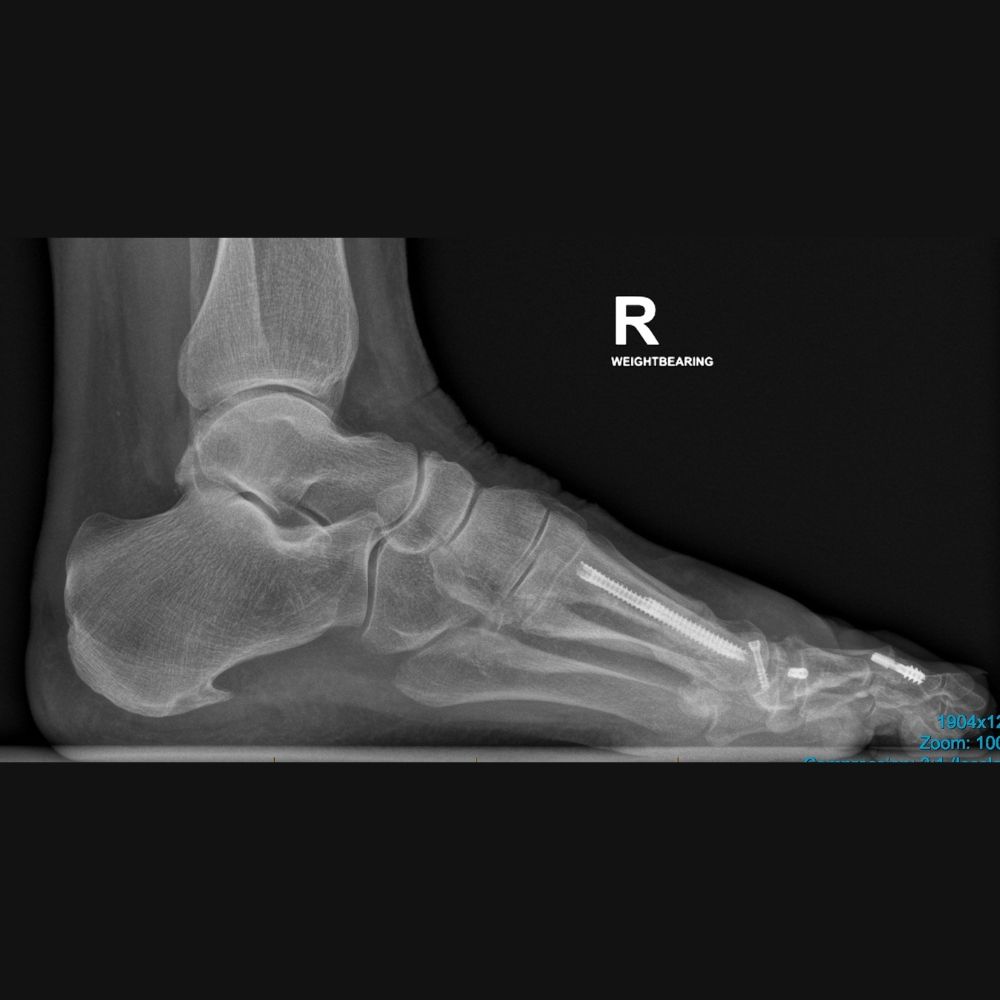

Adult Patient with Minimally Invasive Bunion Correction and Hammer Toe Correction for Metatarsalgia